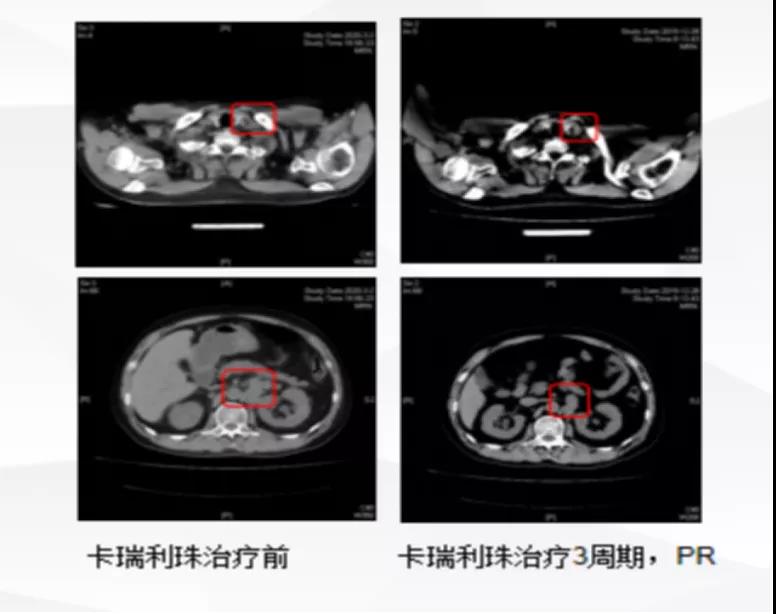

患者,金XX,男,65岁。于2017-11-30 CT发现:膀胱占位伴后下纵隔、腹膜后及左侧髂血管旁多发淋巴结转移,侵犯左输尿管入口伴左肾、左侧输尿管轻度积水。因...